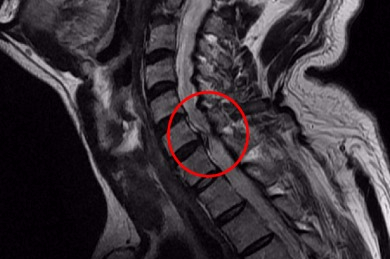

목 디스크는 목의 디스크(경추 디스크)에서 출현하는 질환으로, 경추 디스크 사이의 연골판이 터져 디스크 내부 물질이 경추 신경을 자극해 통증이나 저림증 등의 증상을 유발 해요. 목 디스크는 일상생활에서의 안 좋은 자세나 많은 운동, 부상 등이 이유가 되는 것이 될 수 있기도하고, 시간이 지날수록 발생 확률이 높아져요. 목 디스크의 증상으로는 목 부위의 통증, 팔의 저림, 근육 약화 등이 있으며, 증상이 난폭한 경우 수술 등의 치료가 필요할 수 있어요. 그리하나 대개의 경우 치료 없이도 시간이 지나면 증상이 호전되는 경우가 대부분입니다.

추간판의 수핵이 빠지거나 퇴행성 경추증 및 경추관협착증 등으로 척수가 압박되면 대다수 팔에 힘이 빠지는 것을 느끼게 돼요. 척수가 눌리는 정도이기 때문에 한쪽 팔만 마비될 수 있고요. 하지마는 양팔의 감각이 둔해지고 눈을 감고도 어지럽기 때문에 이러한 목 디스크 증상이 나타나면 무척 위험한 상태가 되기 때문에 빨리 치료가 필요해요.

척수라는 중추 신경은 목뼈를 통과해 목 아래 감각과 운동 신경에 영향을 끼치기 때문에 목 디스크 증상들이 나타나면 신속하고 빠른 대처가 필요해요. 목디스크 치료형식으로 주로 초기 스탭에는 물리치료나 약물을 통해 대개의 환자들이 호전돼요. 그렇지 않다고 하면 신경 성형술과 차단술이라고 부르는 뼈주사 목디스크 치료방법을 이용하는데, 이 치료방법은 통증이 있는 신경 부위에 약물을 삽입하는 것입니다.

시술로써 눈에 띄게 질환을 현저히 치료하시는 것이 아니라 염증을 보완하고 통증을 낮추는 것이 포인트입니다. 이러한 방식으로 비 수술적인 치료를 3개월 이상 넘었음에도 불구하며 증상이 호전을 보이지 않으신다면 목디스크 치료방법 중 수술적 치료를 고심해야 하더라고요. 인공디스크를 투입하기 위함으로 절개를 통하기에 디스크를 제거하며 뼈를 하나로 유합 시켜서하는 것과, 내시경 수술로 빠져 나온 수핵 자체만을 제거시켜서하는 방법이 있다고하고요.